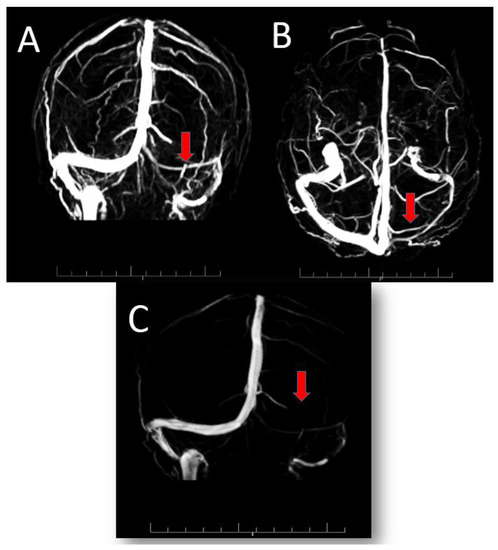

No abnormalities were detected on echocardiography, arterial and venous ultrasound Doppler in the lower limbs, abdominal ultrasound, ultrasound Doppler of the supra-aortic vessels, and CT scan of the chest and brain. At MRI angiography of the intra and extracranial vessels, no relevant abnormalities were found, while in the venous phase only a hypoplasia of the left transverse sinus was found, in the absence of thrombus (Figure 1).

Figure 1.

3D reconstruction of venous angio-RM showing hypoplasia of left transverse sinus, indicated in (A) (Coronal), (B) (Caudocranial) and (C) (Sagittal) figures by the red arrows, in the absence of thrombus.